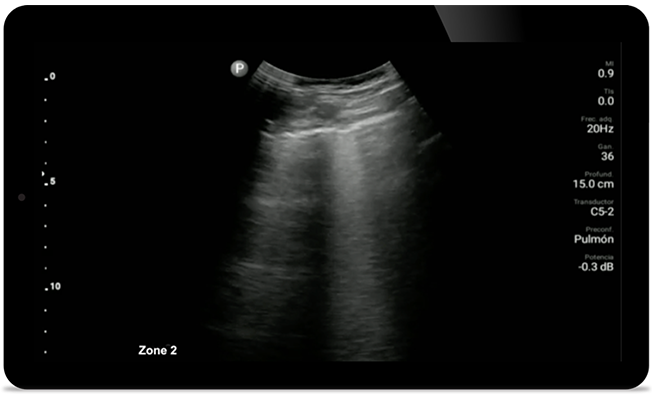

Lumify can help give results similar to a chest CT when evaluating pneumonia and adult respiratory distress syndrome.

Lumify L12-4 broadband linear array transducer

• 12 to 4 MHz extended operating frequency range

• Aperture size: 34mm

• 2D, steerable color Doppler, M-mode, advanced XRES and multivariate harmonic imaging, SonoCT

• High resolution imaging for shallow applications: soft tissue, vascular, superficial, musculoskeletal, and lung